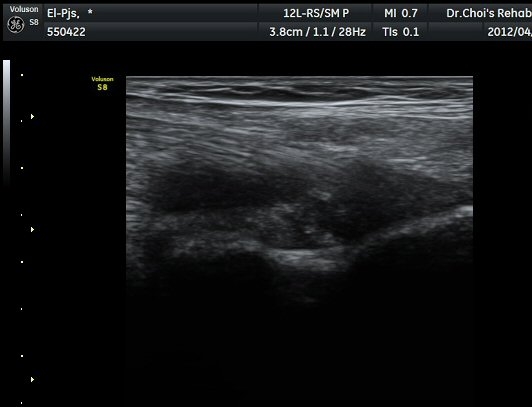

ŽÃËÀÚ¸¦ ÆÈ²ÞÄ¡ ¸»´ÜÀ¸·Î À̵¿ÇÏ´Ï À̵ιڱ٠ÈûÁÙÀÇ ºñÈÄ¿Í ÈûÁÙ ÁÖÀ§¿¡ Àú¿¡ÄÚ ¼ö¾×Àú·ù°¡ ]

°üÂûµÈ´Ù(±×¸² 2, 3, 4, 5). ŽÃËÀÚ¸¦ ¸»´ÜÀ¸·Î À̵¿ÇÒ ¶§ ŽÃËÀÚ¸¦ ¸Ó¸®ÂÊÀ¸·Î °æ»ç(tilting)½ÃÄѾß

À̵ιڱ٠ÈûÁÙ¿¡ Á÷°¢ ÀÇ ÃÊÀ½ÆÄ Á¶»ç°¡ °¡´ÉÇÏ¿© À̵ιڱ٠ÈûÁÙÀÌ °í¿¡ÄÚ·Î °üÂûµÈ´Ù.